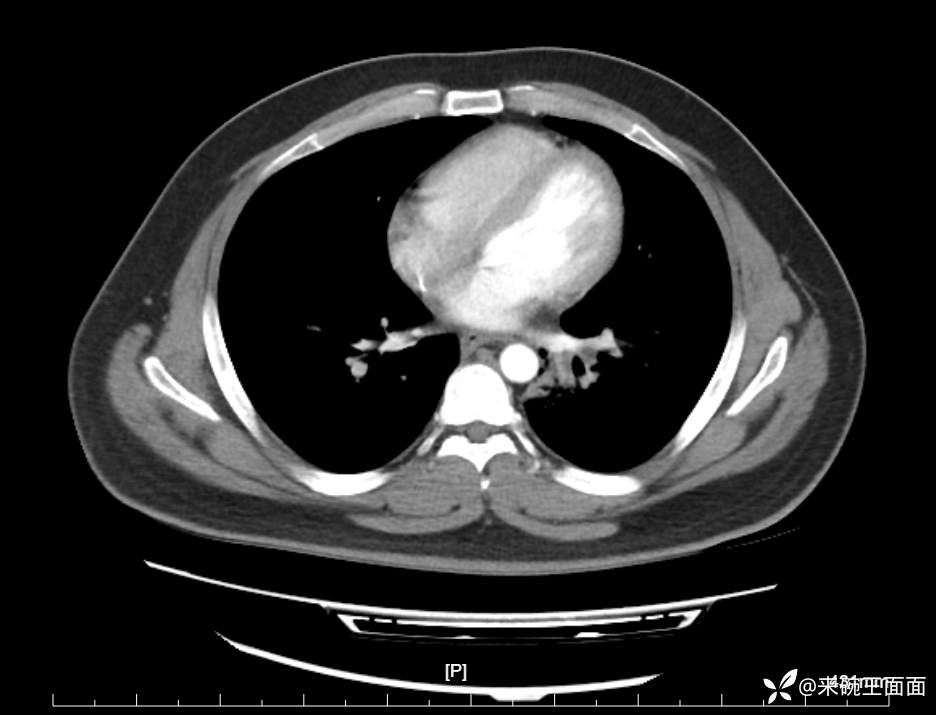

性别:男

年龄:27岁

主诉:胸闷胸痛数月余,休息后可自行缓解,无咯血症状。

个人史:数年吸烟史,具体不详。